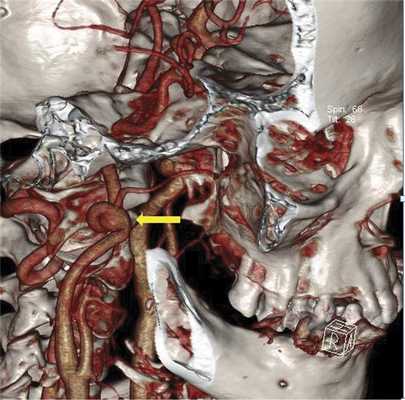

При принятии решения о выборе метода хирургического вмешательства помимо общеклинических обследований учитывались данные дуплексного сканирования брахицефальных артерий (ДС БЦА), транскраниальной допплерографии (ТКДГ), мультиспиральной компьютерной томографической ангиографии (МСКТ-ангиографии) и магнитно-резонансной томографии (МРТ) головного мозга. По результатам ДС БЦА у всех пациентов выявлено нарушение хода ВСА в виде патологической извитости различной формы с ЛСК от 150 до 230 см/с. Аневризматическое расширение по данным УЗИ выявлено только в 1 случае. Более полная информация была получена по данным МСКТ-ангиографии экстра- и интракраниальных артерий, при которой во всех случаях выявлена патологическая извитость дистального отдела ВСА различной степени выраженности. В 2 случаях на уровне атланто-аксиального сочленения определялись мешотчатые аневризмы размером 8 и 12 мм, с частичным тромбированием аневризматического мешка (рис. 1). В 1 наблюдении выше аневризмы определялся участок надрыва интимы с фузиформным расширением дистального отдела ВСА.

Рис. 1. МСКТ-3D ангиография БЦА. Стрелкой указана дистально расположенная аневризма ВСА в сочетании с патологической извитостью артерии.